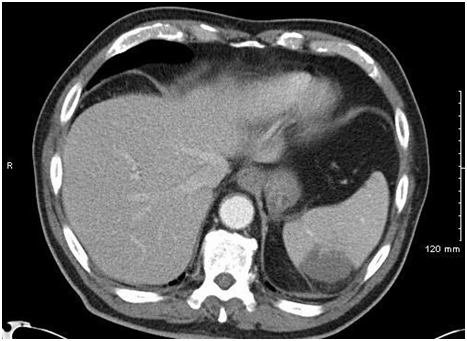

79 year old Hispanic male with past medical history of HTN and osteoarthritis presented to the emergency room complaining of left side abdominal pain for three days and intermittent confusion. Physical examination was unremarkable apart from fluctuating mental status and left lower quadrant tenderness on palpation of abdomen. Initial laboratory investigations revealed anemia, thrombocytopenia, elevated bilirubin but normal liver enzymes and lipase. The peripheral blood smear showed schistocytes. Imaging studies including abdominal Computed Tomography (CT) scan demonstrated a wedge-shaped hypo-enhancing lesions in the spleen typical for splenic infarcts as shown in Figure 1 and a brain CT scan was unremarkable.

Figure 1 Computed Tomography scan of the Abdomen showing wedge-shaped hypo-enhancing lesion in the spleen.